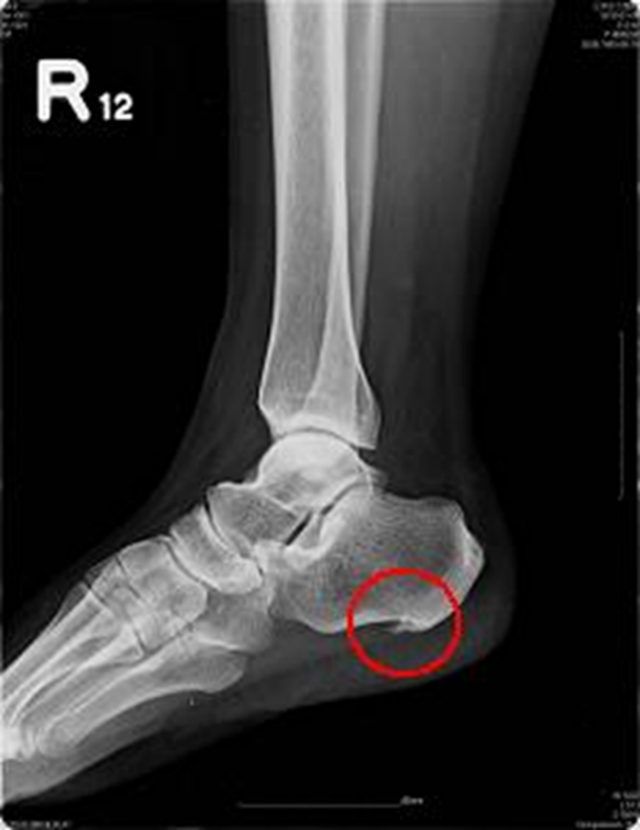

足跟痛症

由于日常生活中过度劳累、劳损,或者是由于到了一定的年龄,足跟脂肪垫、跟腱变性、跟骨结节骨膜炎症、跟骨骨刺等导致足跟周围疼痛为表现的一类疾病。